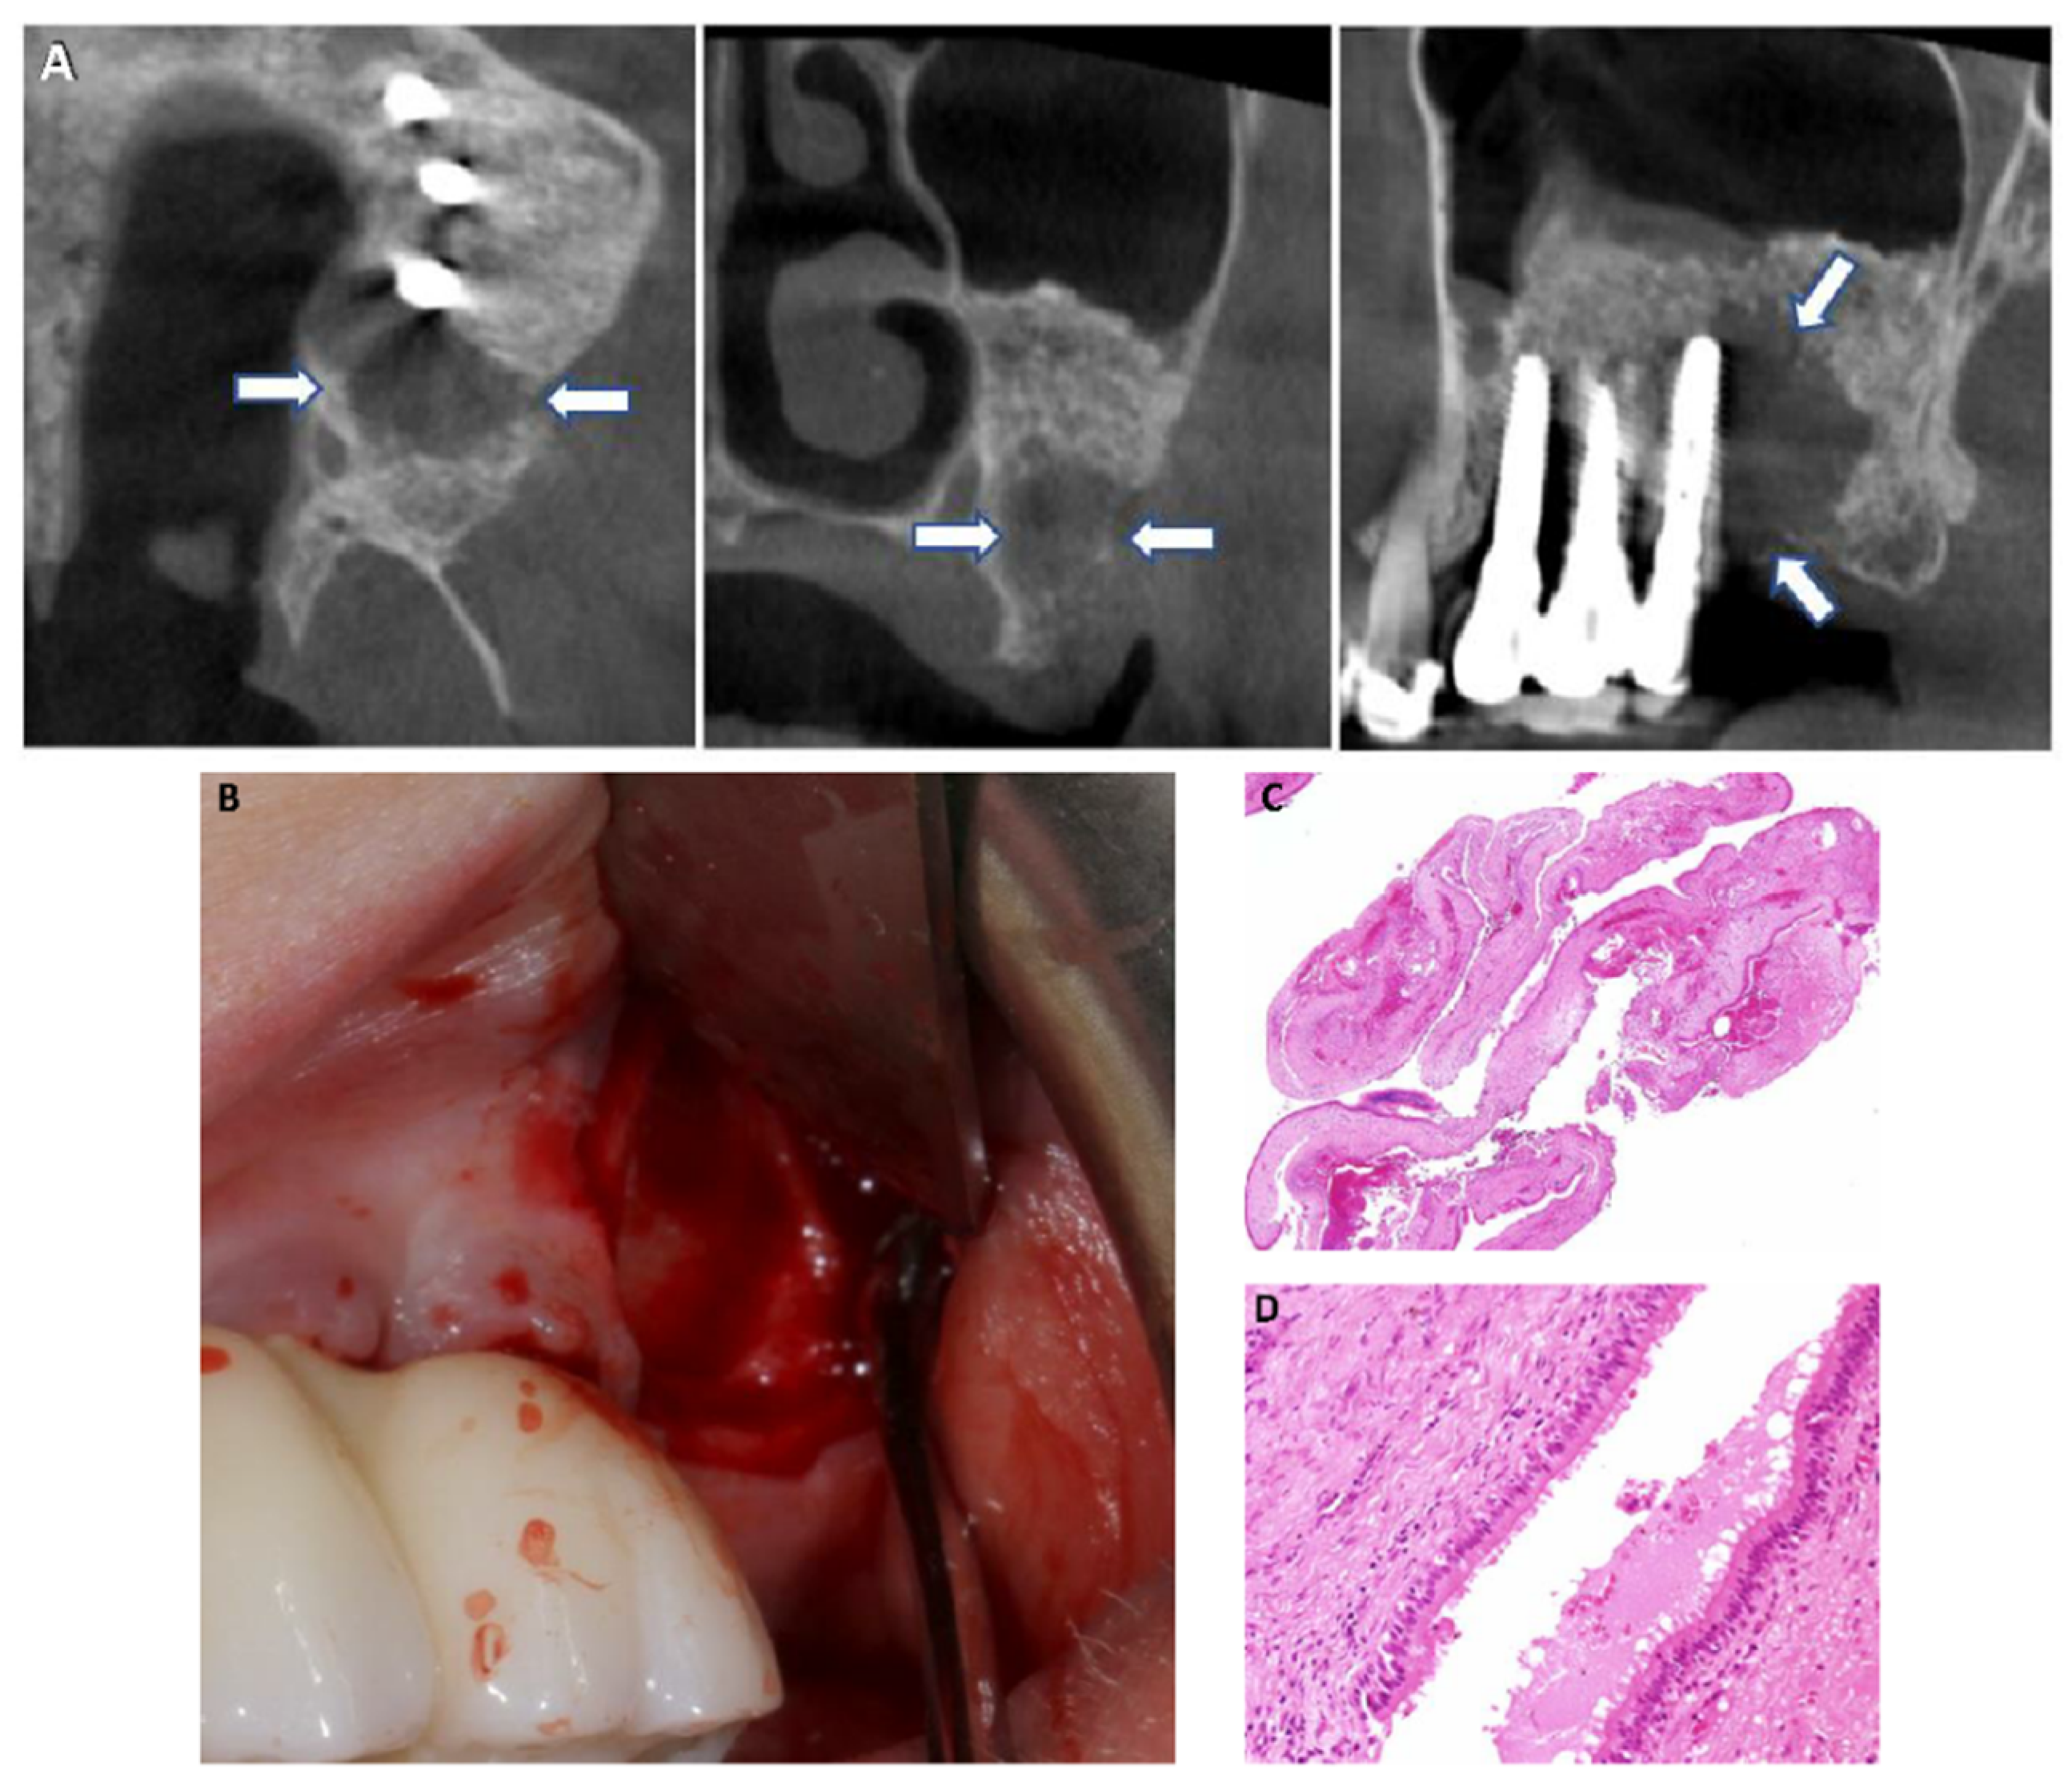

3.1. Case Description

3.1.1. Case 1

3.1.2. Case 2

3.1.3. Case 3

3.1.4. Case 4